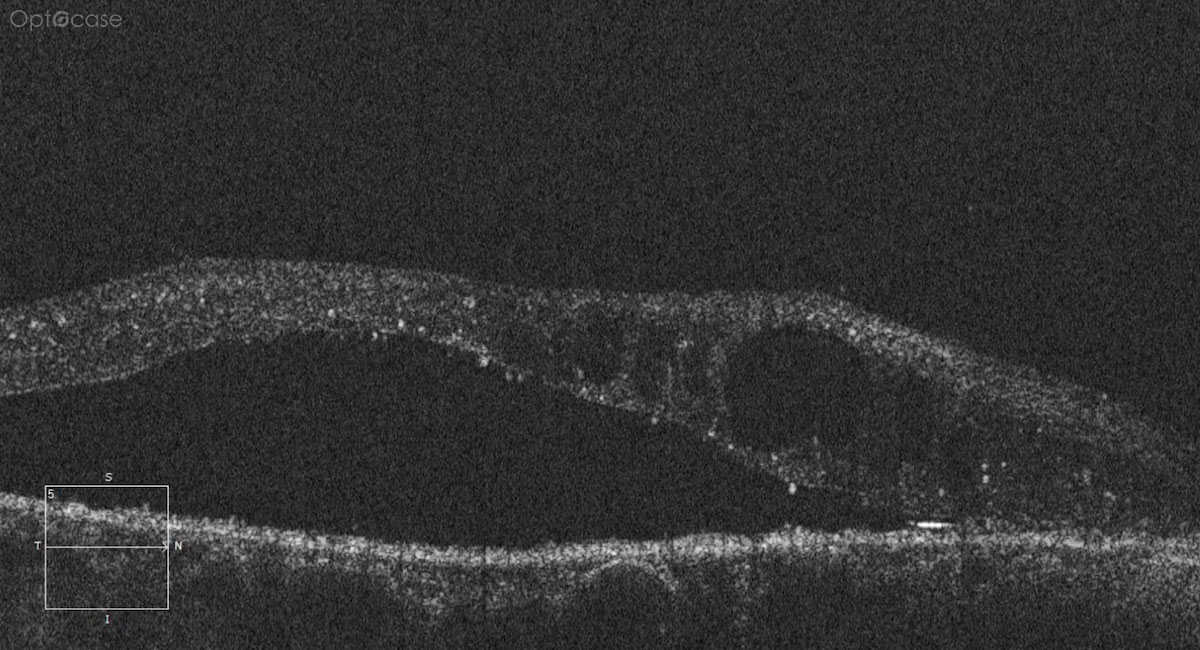

This patient was diagnosed with a CNV secondary to Ocular Histoplasmosis.

In a patient with a CNV, look at the mid-periphery and look for punched out lesions consistent with ocular histoplasmosis